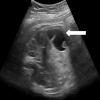

Figure 1

une image abdominale kystique anéchogène de 3 cm bien limitée latéralisée à gauche, à paroi propre, non vascularisée au doppler